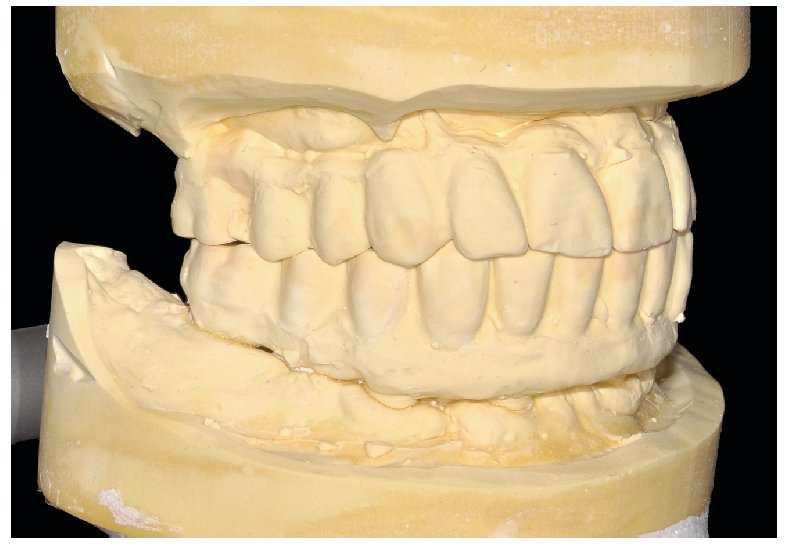

La retirada de las restauraciones protésicas de la cavidad oral para estos controles brinda la posibilidad de montarlas en el articulador empleando una técnica de montaje cruzado (figs. 83 a 85). De esta manera se evita la pérdida de todas las valiosas informaciones acumuladas al principio y en el curso del tratamiento.

Fig. 83. Los modelos de las restauraciones prequirúrgicas montados en el articulador.